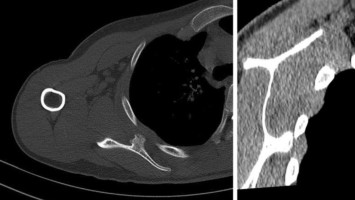

Bei einem 21-jährigen Patienten traten nach einem Sturz beim Uni-Hockey starke Schmerzen auf, nachdem sich die Schulter ohne fremde Hilfe reponierte. Der linke Arm wurde in einer Innenrotationsschonhaltung gehalten. Erkennen Sie die seltene Schulterverletzung?